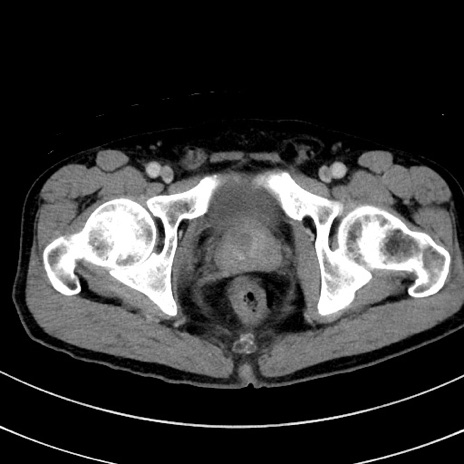

症例8(横断像)

【症例】 60歳代男性

【主訴】 黒色吐物

【現病歴】 4日前から嘔気自覚、2日前の朝食後にも嘔気あり、自分で手で嘔吐反射起こし嘔吐したところ血が混ざっていたため受診。

【既往歴】 5年前汎発性腹膜炎を伴う急性虫垂炎で手術、高血圧、前立腺肥大症、高脂血症

【身体所見】 腹部正中に手術癩痕あり 腹部平坦・軟圧痛なし膨満感あり

【データ】WBC 8400、CRP 4.54